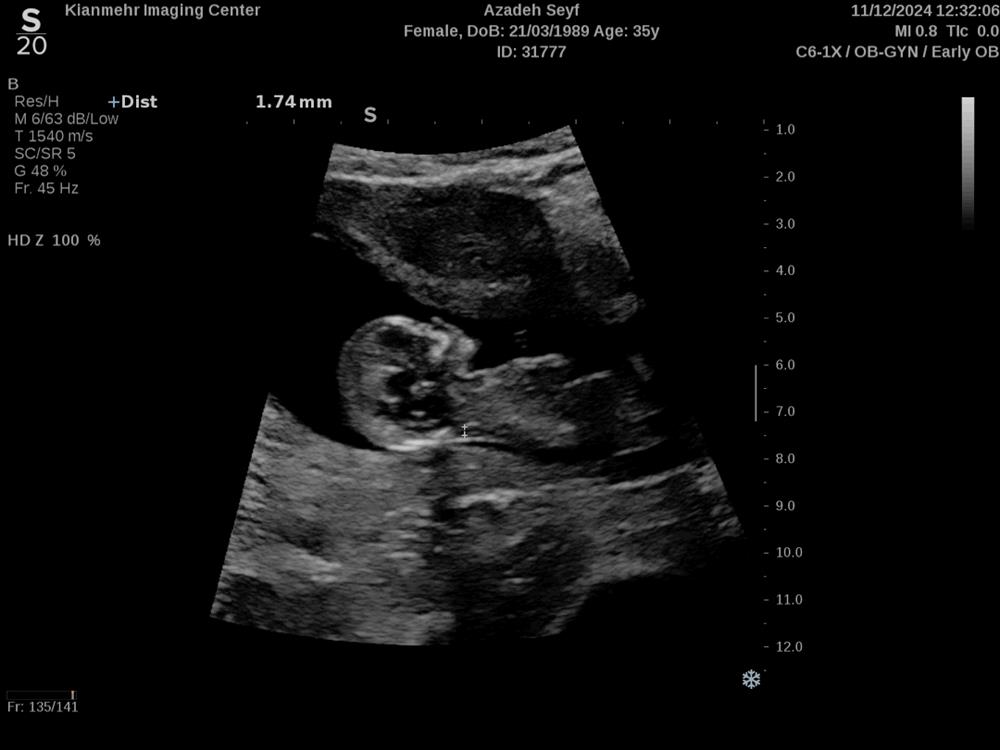

azi6813 مدیر عضویت: 1400/09/08 تعداد پست: 265 عنوان جنسیت از روی سونو ان تی | مشاهده متن کامل بحث + 160 بازدید | 16 پست سلام بچه ها کسی از رو عکس سونو میتونه جنسیت رو بگه 1403/09/22 | 12:32 0 نفر لایک کرده اند ... گزارش تاپیک نامناسب

مادرویانا عضویت: 1400/08/23 تعداد پست: 1160 سلام دختره خدا حفظش کنه ، ان شاء الله همیشه سلامت باشه خداجونم ممنونم که به آسانی و زیبایی و عزتمندانه بهم فرزند سالم و صالح و نابغه و مهربان عطا کردی، خدایا سپاس گذارم